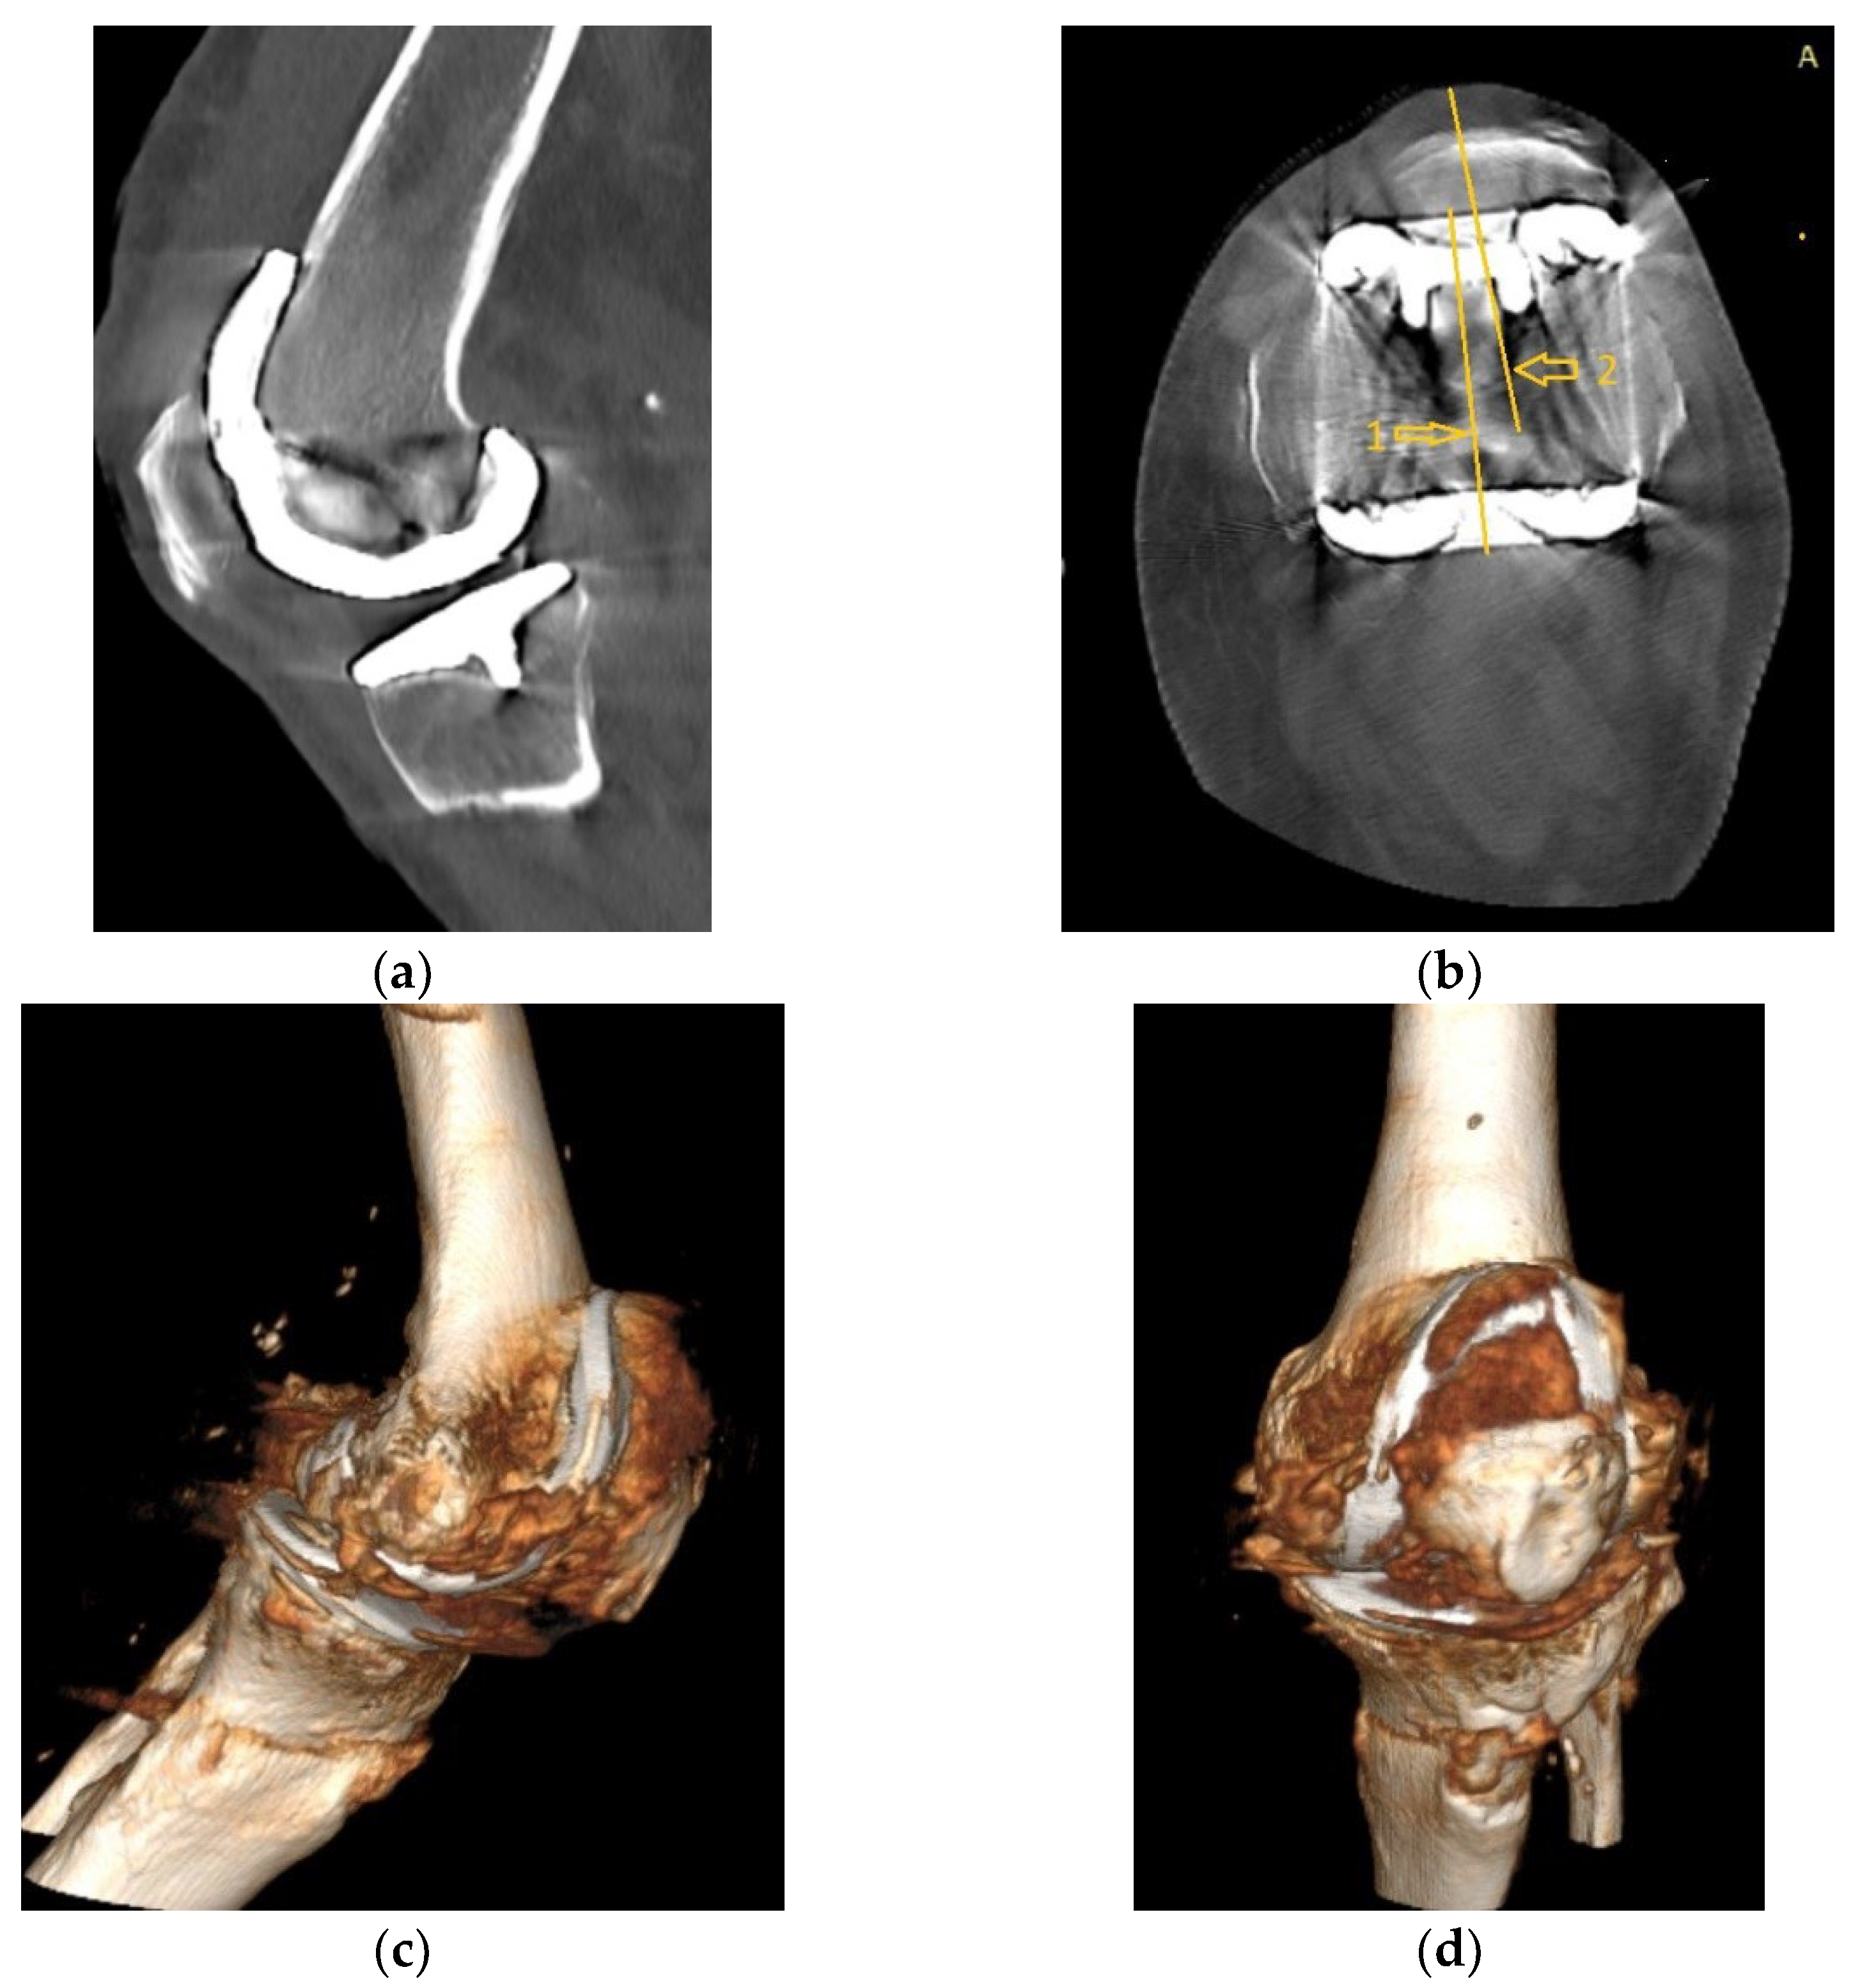

Alongside with the clinical scores, the patient was also evaluated radiologically, with CT scans and standard X-rays. Radiological investigations, using coronal, lateral and axial views (Merchant view) showed patellar arthrosis and a slight lateral subluxation of the patella (Figure 4).

Figure 4.

(a) coronal view, patellar lateral subluxation (arrow) compared to femoral axis with (1) marking the femoral trochlear axis, (2) patellar axis and (3) the patella must be centered in the femoral trochlea; (b) lateral view, patellar wear, patellar trochlea deformation and subchondral bone condensation with (4) marking subchondral osteocondensation and (5) patella bone deformation; (c) axial view, patellar lateral subluxation, and deformation, osteocondesation of the subchondral bone with (6) patella bone deformation and condensation, (7) femoral trochlear axis and (8) Patellar axis.

CT images, subject to artifacts generated by the implant, show patellar wear and peripatellar inflammatory phenomena (Figure 5).

Figure 5.

CT images: (a) Sagittal view showing patellar arthrosis, condensation of subchondral bone. (b) Axial view showing patellar arthrosis, deformation, and lateral subluxation (arrow) with (1) marking the femoral trochlear axis and (2) patellar axis; (c,d) CT 3D image, peripatellar inflammation.